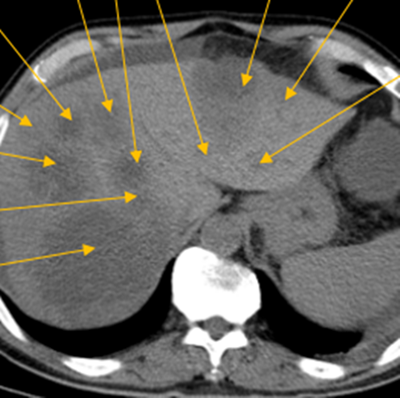

組織腸癌MDT診療團(tuán)隊(duì)進(jìn)行病情討論,診斷為腸癌伴肝、肺、腹腔、縱膈轉(zhuǎn)移,其中肝轉(zhuǎn)移瘤數(shù)目在50枚以上,最大的約10cm,并伴有腸梗阻,情況不容樂觀。

隨后,根據(jù)基因檢測結(jié)果制定了化療+靶向治療方案。經(jīng)過精準(zhǔn)治療,劉大爺?shù)牟≡畲笮⊙杆倏s小,病灶數(shù)量不斷減少,影像學(xué)評(píng)估已經(jīng)看不見之前那些小的病灶了。

治療前:箭頭處均為轉(zhuǎn)移性腫瘤